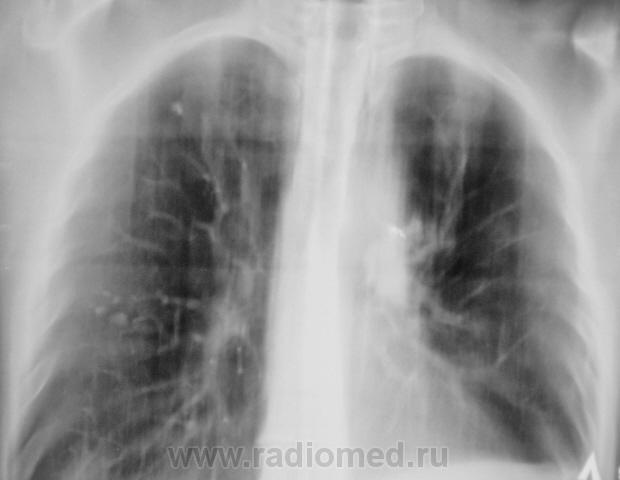

На обзорной рентгенографии ОГК определяется единичный очаг в первом межреберье справа, и множественные очаги в пятом межреберье справа! Правый реберно-диафрагмальный угол спаян! Ателектаз левого легкого? В корне левого легкого определяется тень неправильной формы! Центральный рак? Метастазы? Туберкулез?

А левая верхушка? На томограммах тоже видны изменения.А в корне левого легкого это швы?( почему-то снимки не увеличиваются).Левый корень плотный.Не исключено наличие ателектаза в язычковых сегментах ( или инфильтрации).Боковые будут?Хотелось бы.

Оперирован. Левостороняя лобъектомия по поводу больших размеров туберкуломы. Архива у нас нет, он в "областной конторе".

Думаю, рецидив ТБС. Оперированное левое легкое.

Рецидив справа?

С обеих сторон.

Золотые слова. Коллега фтизиатр, увидев, эти новые снимки очень расстроился и сказал непотребное слово на букву "б", очень расстроился, рецидив, как "пить дать"...

Да, скорей всего получается рецидив. И всё же архив посмотреть надо.